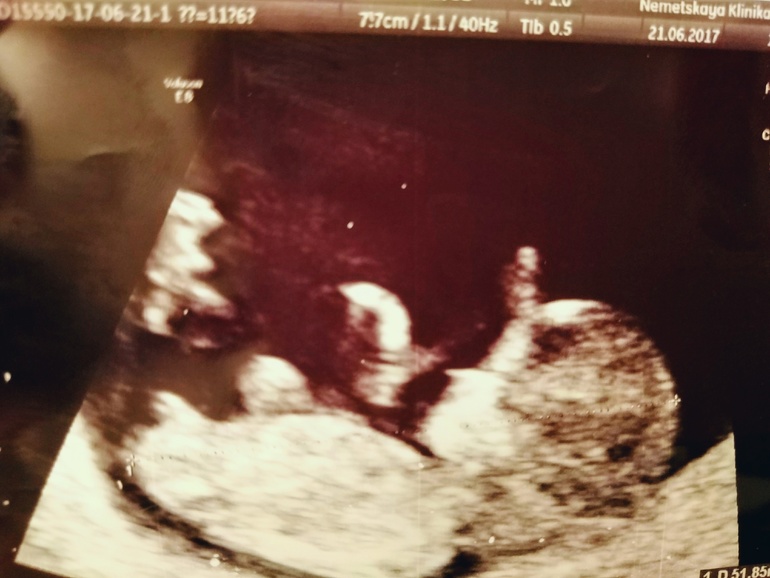

Мальчик?

УЗИ, КТГ, доплерВрач УЗИ на скрининге уверенно сказал, что пол мужской, срок 12 недель. В ответ на мое сомнение улыбнулся и сказал, что на 85% уверен в этом. Кто разбирается, не превратится наш "мальчик" ещё в девочку?)

Аппарат очень хороший, врач Понкрашкин, Санкт-Петербург.